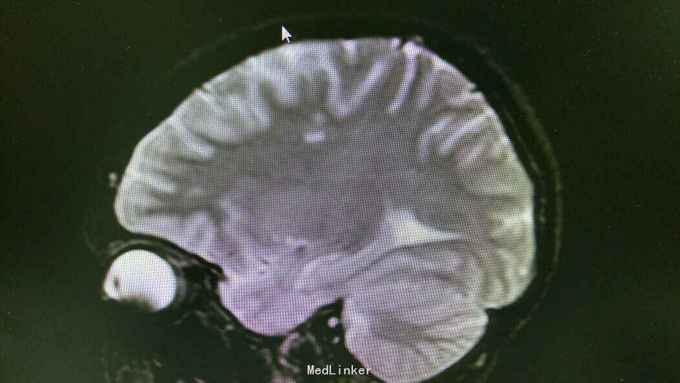

查体:T37.0℃,P110次/分,R26次/分,BP96/68mmHg。发育正常,营养一般,神志清楚,对答切题,轮椅送入院,查体合作。全身皮肤粘膜无黄染、皮疹,出血点及淤斑,未见Janeway结节,未见Osler结节及甲床下出血,无发绀,未见杵状指、趾,周围血管征阴性。浅表淋巴结未及肿大。巩膜无黄染,结膜无出血。口腔黏膜光滑,咽不红,扁桃体部大,颈静脉无明显搏动,未见怒张,气管居中,胸背部听诊双下肺闻及细小湿啰音。心前区无隆起或抬举性搏动,心尖搏动以左侧第六肋间锁骨中线外1.5cm处明显,未扪及震颤,心界向两侧稍扩大,心率110次/分,律齐,心音有力,P2稍亢进,无固定分裂,心尖区闻及3-4/6级收缩期吹风样杂音,向心底部传导,未闻及舒张期杂音,未闻及心包摩擦音。腹平软,无压痛及反跳痛,肝脾肋下未及,肠鸣音正常。脊柱、四肢关节无异常,活动好,双下肢无浮肿。 2015年10月30日汕头市中心医院心彩超:二尖瓣及瓣下腱索及左室心内膜多发赘生物形成,二尖瓣前瓣穿孔,重度二尖瓣关闭不全,左心系统扩大,心肌舒张功能下降,收缩功能正常,感染性细菌性心内膜炎,微量心包积液。 2015-11-1血常规:中性粒细胞比例 0.949,血红蛋白浓度 117.000(g/L),中性粒细胞计数 18.360(10E9/L),白细胞计数 19.350(10E9/L),血小板计数 343.000(10E9/L),红细胞计数 4.350(10E12/L)。 B超:双侧颈动脉血流通畅,双侧椎动脉未见狭窄。双侧甲状腺不大、未见占位,血供尚丰富。双侧颈部淋巴结声像,双侧乳腺未见明显占位,超声BI-RADS分类1类,双侧腋窝淋巴结声像。双肾未见结石与积水,双肾动脉主干血流连续,膀胱未见明显结石,双侧肾上腺区未见明显占位。肝脾胰不大,未见占位,胆囊未见明显结石,子宫及双侧附件区未见明显占位,宫后积液(少量)。 胸部CT:1、两下肺叶后基底段局部节段性肺炎。右肺中叶少许纤维化病灶。2、双侧胸腔少量积液。 胸片:考虑双肺炎症。 心电图:心率84次/分,窦性心律,肢体导联低电压,前间壁R波上升不良。 心彩超:1、考虑感染性心内膜炎:二尖瓣赘生物形成,伴中重度二尖瓣反流。中度三尖瓣反流。3、左房内径增大,肺动脉增宽。 头颅MR:左侧额叶、左侧放射冠侧脑室前角旁脑白质异常信号,考虑感染性病变及缺血灶可能性大。 2015-11-2查血常规:中性粒细胞比例 0.840,血红蛋白浓度 103.000(g/L),中性粒细胞计数 14.730(10E9/L),白细胞计数 17.540(10E9/L),红细胞计数 3.890(10E12/L),血小板计数 353.000(10E9/L)。 10月31日左上肢、右上肢、下肢血培养均提示:草绿色链球菌,对万古霉素敏感。 2015-11-6肾功能:肌酐 130.000(umol/L),尿素氮 5.250(mmol/L),二氧化碳结合力 30.500(mmol/L),电解质:钠 138.000(mmol/L),氯 96.000(mmol/L),钾 3.500(mmol/L),钙 2.310(mmol/L),肝功能:白、球蛋白比例 1.300,未结合胆红素 10.500(umol/L),总胆红素 17.900(umol/L),丙氨酸氨基转移酶 31.000(U/L),总蛋白 75.000(g/L),球蛋白 32.000(g/L),白蛋白 43.000(g/L),结合胆红素 7.400(umol/L),门冬氨酸氨基转移酶 31.000(U/L),脑钠肽:191.400(pg/ml)。 24小时心电图:窦性心律,房性早搏,部分成对,短阵房速,多源室早,部分成对,部分呈三联律,短阵室速。

关于感染性心内膜炎此前我发布过一个病例,但不同的病例有不同的特点和经验教训。上次的病例病变范围大,累及多瓣膜,治疗的难度在手术关,因手术过程复杂、手术时间长、对患者全身打击影响大,但上一个病例术前感染控制良好,在全身情况明显好转的情况下手术。此次发布的这个病例赘生物累及的瓣膜无上例多,但本例患者术前感染无法控制,反复高热、寒战,且赘生物大且形态呈“甩鞭样”,随时可能脱落栓塞周围脏器,另头颅MR报告左侧额叶、左侧放射冠侧脑室前角旁脑白质异常信号,考虑已有部分小栓子脱落栓塞脑血管形成小的感染性病变及缺血灶可能性大。因此综合考虑上述因素决定无法等患者全身状态好转在所谓的“理想状态”下手术,必须冒风险尽快行手术治疗,否则患者全身情况会进一步恶化并且可能发生脑栓塞,因此失去手术时机并可能导致死亡。术中需仔细清除干净感染的赘生物,术后积极强心、利尿、支持治疗并且敏感抗生素治疗4周。该病例术后出现反复双侧胸腔积液及心包积液,上一个病例也曾出现胸腔积液,考虑与患者术前全身状况不佳、心功能差及感染性心内膜炎所致的全身败血症及感染微栓有关。